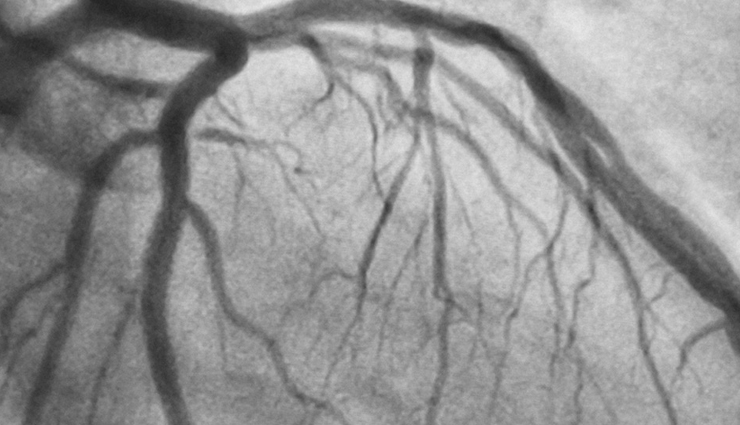

# Coronary angiogram

A type of X-ray used to examine the coronary arteries supplying blood to your heart. A catheter is inserted into a blood vessel in your arm or groin and fed up to your heart and coronary arteries. Special dye is then injected through the catheter and images are taken.

Reasons for the tests:

- Identify narrowing or blockages in the coronary arteries

- Evaluate pressures inside the heart